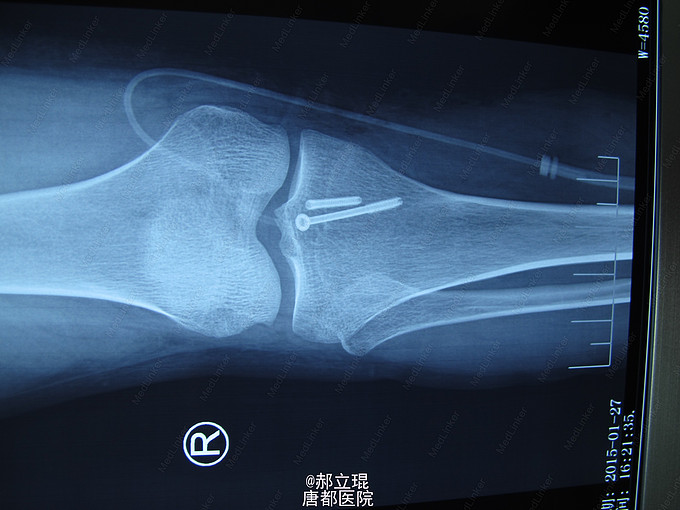

入院后给与影像学检查完善及相关术前准备,于伤后第7天行髁间棘骨折,切开复位内固定术。术后早期功能锻炼。

患者术后6周,膝关节部分负重,3月后完全负重,并膝关节活动功能完全正常。无明显创伤性关节炎的表现。本手术采用后侧入路,于腓肠肌内外侧头间隙入路,手术安全,但要注意血管神经束的保护。术后应早期功能锻炼,同时应用抗凝药物,预防血栓,尤其是腘动脉牵拉造成的血栓。